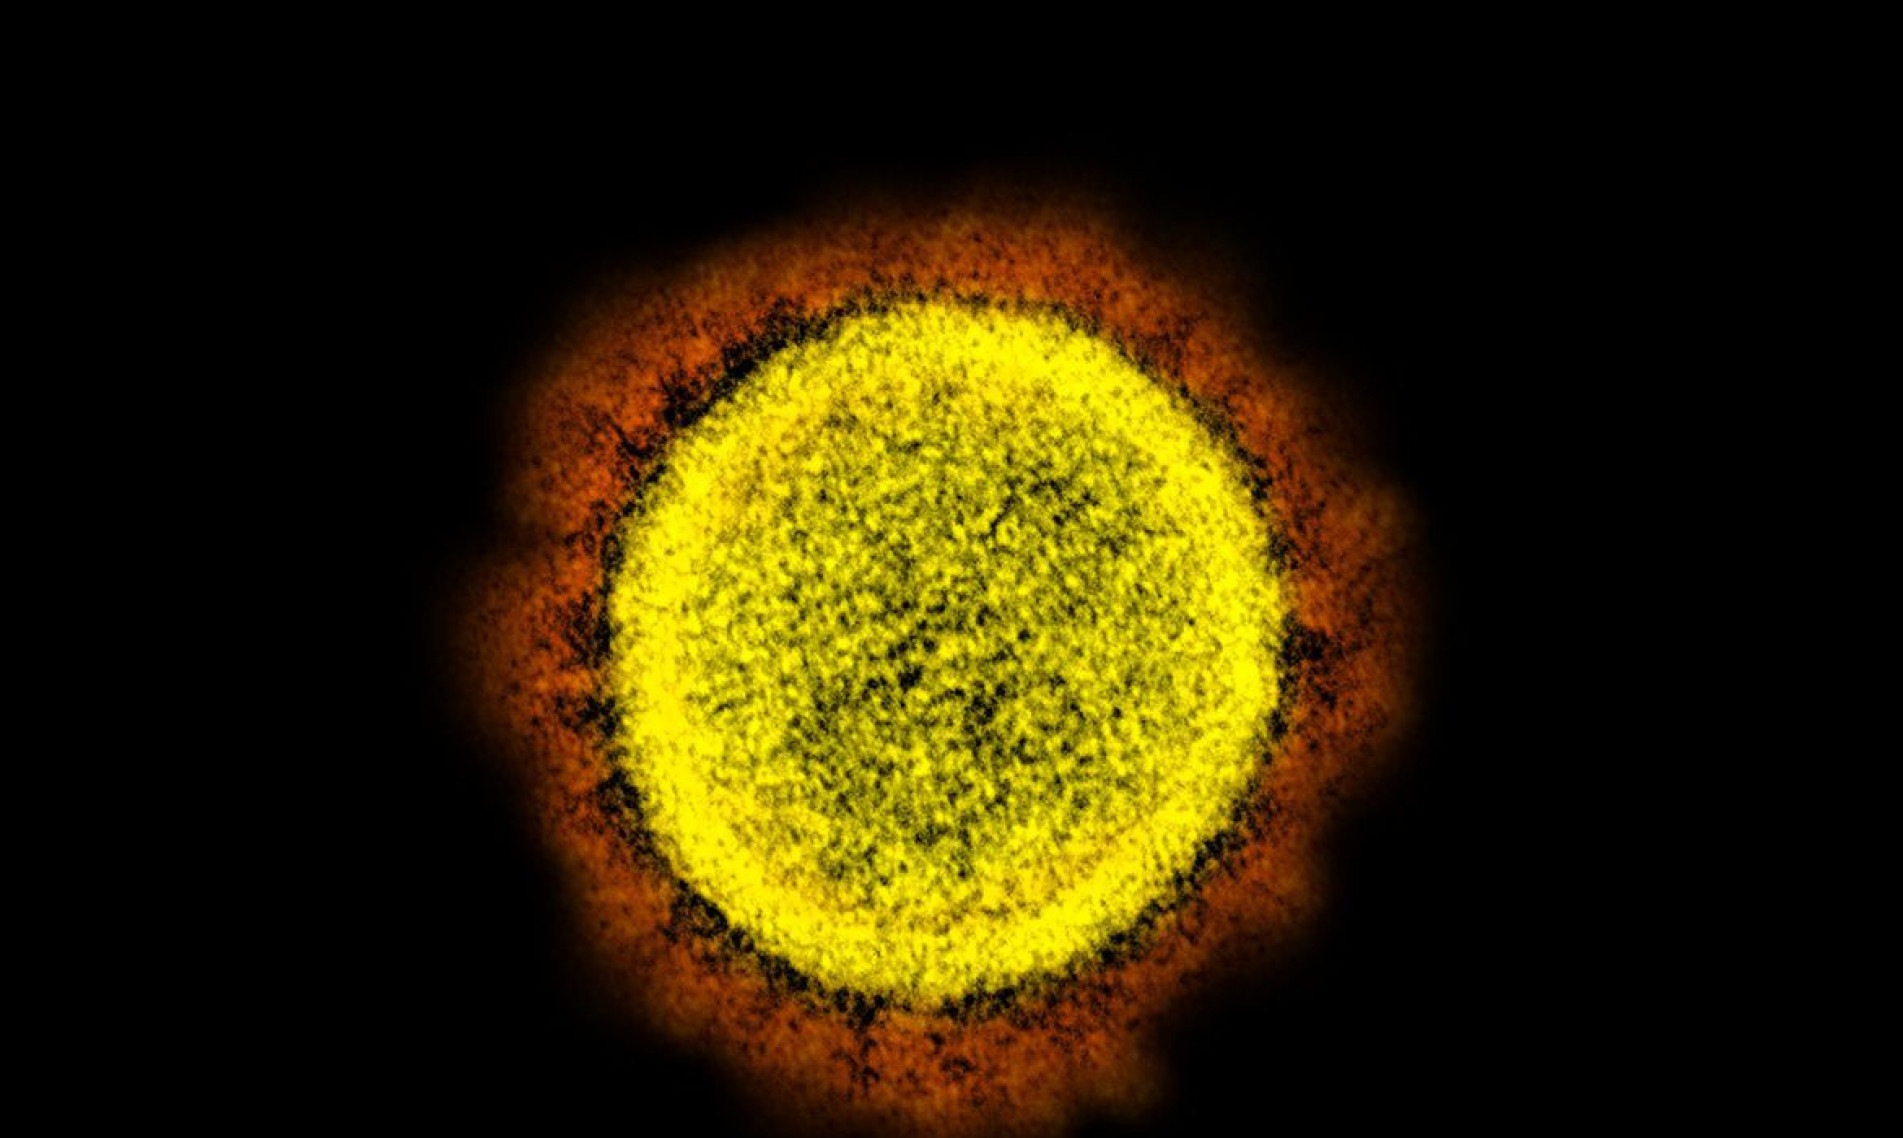

Sobe para 74 o número de casos da variante Ômicron no Brasil

O balanço divulgado nesta quinta-feira (23) pelo Ministério da Saúde indica que foram confirmados 74 casos no Brasil da nova variante do coronavírus, a Ômicron.

As infecções foram registradas em São Paulo (27), em Goiás (22), em Minas Gerais (13), no Rio Grande do Sul (3), no Distrito Federal (1), no Rio de Janeiro (1), no Espírito Santo (1), em Santa Catarina (3) e no Ceará (3).

Há ainda, segundo a pasta, 116 casos em investigação, sendo 16 no Distrito Federal, 19 em Minas Gerais, 58 em Santa Catarina e 23 no Rio Grande do Sul. (Agência Brasil)